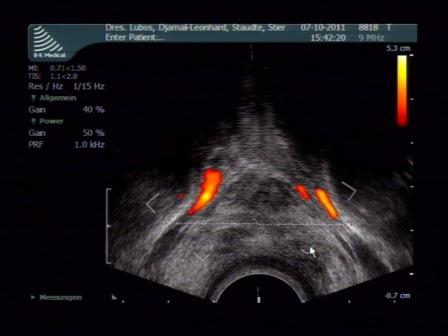

- Endo-Ultraschall mit farbcodierter Duplex-Sonographie und 3-D-Darstellung zur Vermessung, Gewebe- und Durchblutungsanalyse (Untersuchung aller anatomischer Strukturen des Damm-, Sitz- und Sattelbereiches wie Harnblase, Prostata, Harnröhre, After, äußeres Genitale, Nerven- und Blutbahnen sowie Becken- und Schambeinknochen)